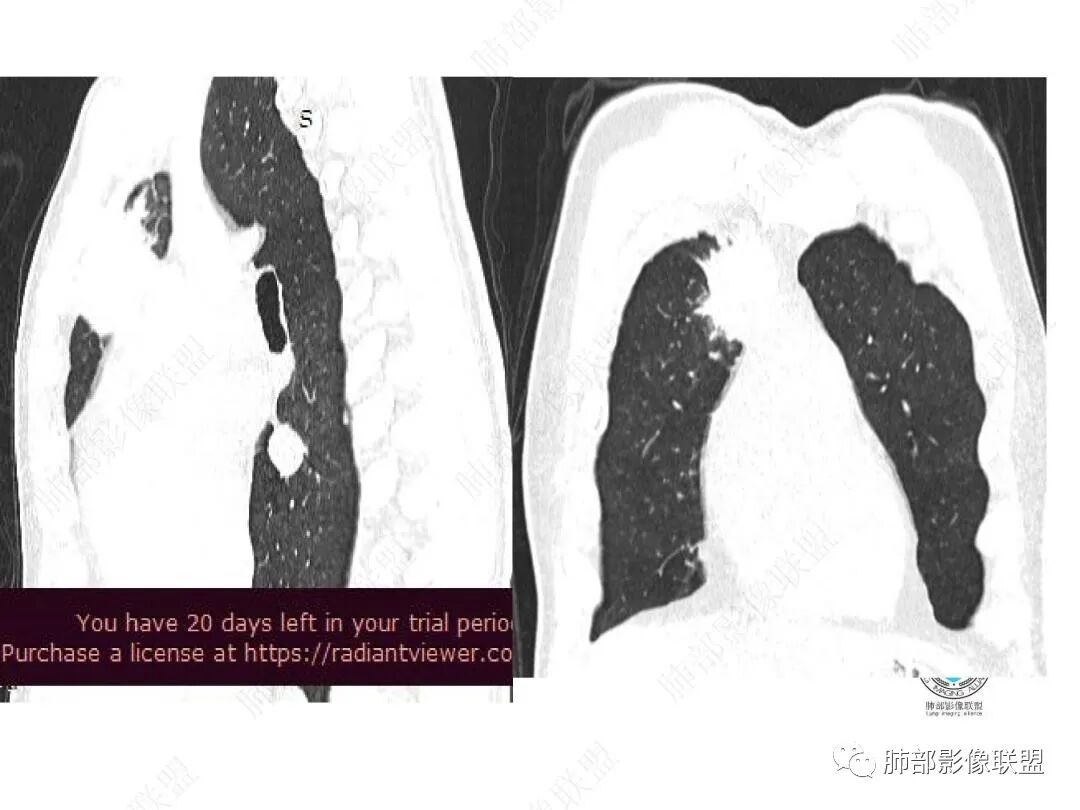

平扫图像

增强图像

右上叶前段胸膜下新发病灶;纵隔淋巴结较前增大

边缘平直,有锯齿状影

支气管进入其中,中近端堵

远端见斑片状高密度影

与胸膜关系:糊墙